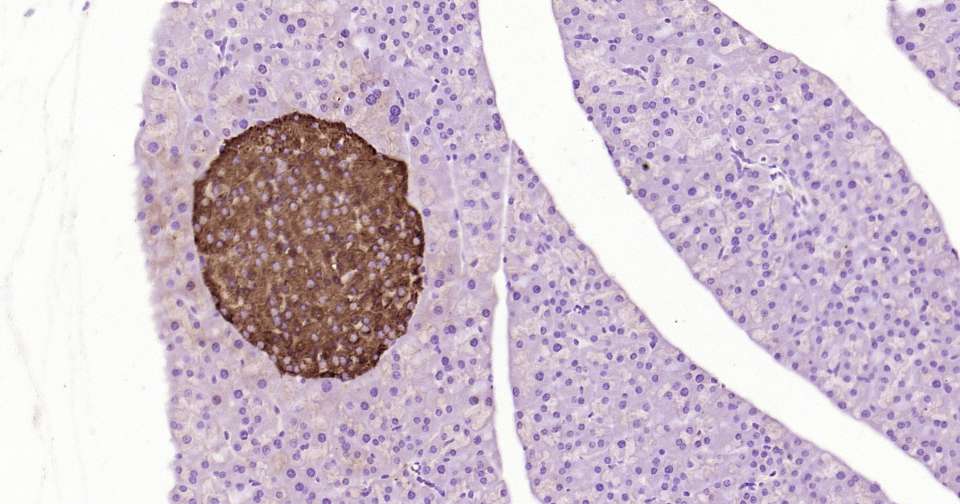

Immunohistochemical analysis of paraffin embedded mouse pancreas tissue slide using IHC0364 (Notch1 Kit).

Immunohistochemical analysis of paraffin embedded human pancreas tissue slide using IHC0364 (Notch1 Kit).

Immunohistochemical analysis of paraffin embedded rat pancreas tissue slide using IHC0364 (Notch1 Kit).